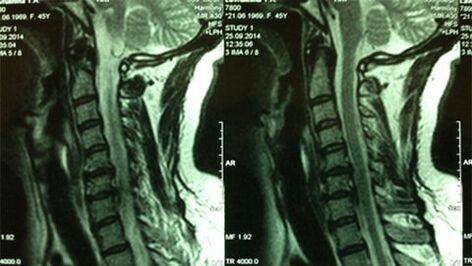

- X -Read of the Cervical Department;In the early stage of the process, the magnetic resonance imaging of the cervical department will be more informative - will ensure high quality visualization of solid and soft tissues - will show the condition of intervertebral discs, the presence of osteophytes, deformations, nerve roots and blood vessels;will evaluate the condition of ligaments, muscles, bone tissue;